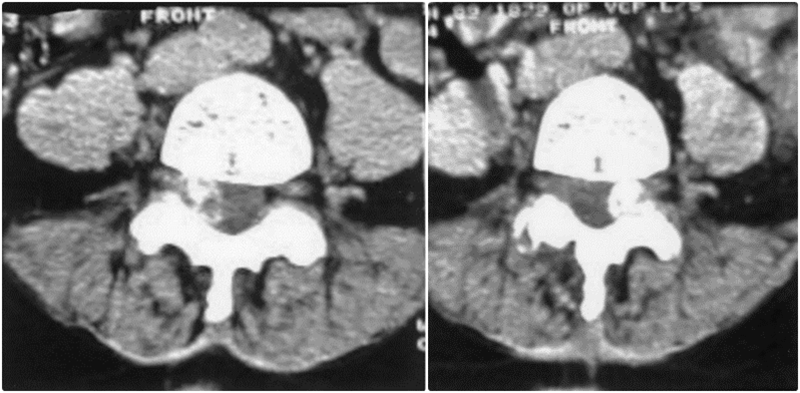

焦磷酸钙沉积疾病引起腰椎双侧症状性滑膜囊肿

CT扫描显示右侧与L4-L5关节突关节相关的钙化滑膜囊肿,明显侵犯椎管

A、注射钆前轴位T1加权MRI扫描显示硬膜囊背侧有低信号钙化肿块移位;B、注射钆后,低信号区周围可见强化环;C、矢状位T2加权MRI图像。箭头显示侧隐窝内有囊性肿块